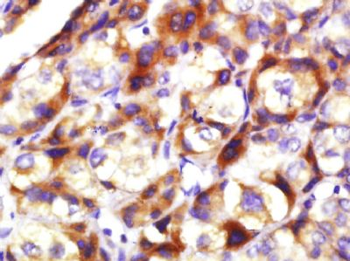

50 μl, 100 μl, 200 μlAnti-Aurora A/AURKA Antibody [orb1290027]

ELISA, FC, IHC, WB

Human

Rabbit

Polyclonal

Unconjugated

10 μg, 100 μgChemerin Rabbit Polyclonal Antibody [orb156351]